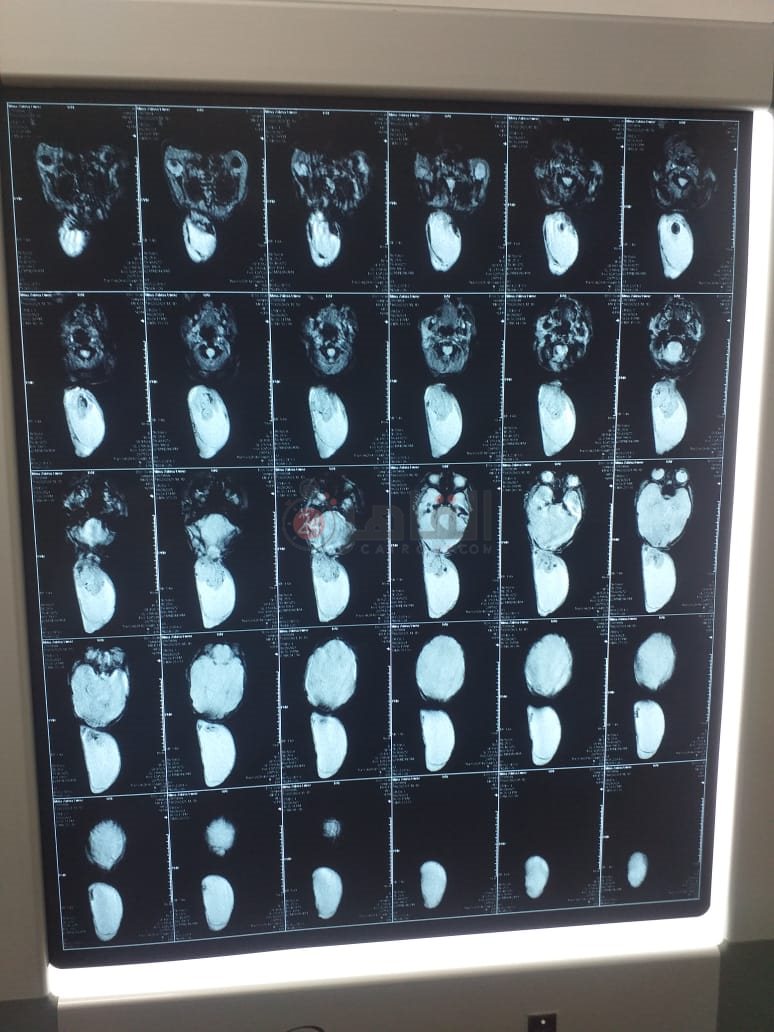

وأكمل زكريا لويس: أجرينا أشعة رنين على رأسه، وتبين حجم الكيس، وما بداخله مياه مع جزء من المخ، وأكد الأطباء ضرورة إجراء عملية جراحية لإزالة الكيس، وطلبنا تحويله من التأمين الصحي في أسوان، على مستشفى أطفال مصر، لكن عندما حضرنها إلى المستشفى؛ أخبرونا بعدم وجود حضَّانة، ولا بد ان ننتظر حتى تتوفر واحدة، والطبيب شدد على الإسراع في إجراء العملية الجراحية بحد أقصى شهر حفاظا على حياة ابني.

وأشار والد الطفل إلى أنه توجه للعديد من المستشفيات في القاهرة، وأجرى أشعة جديدة على رأس الطفل، حيث أكد أحد المستشفيات أنه لا بد من الانتظار شهرين على الأقل، مضيفًا: في مستشفيات قالوا لازم نستنى عشان الجلد يكبر ويكون سميك، لكن حاليًا ظهرت تقرحات على الكيس، وممكن يتفتح بسهولة، وساعتها ابنى هيموت.